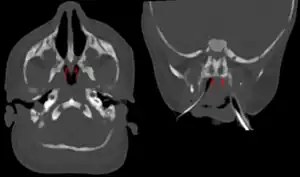

| Bilateral membranous choanal atresia in CT scan | |